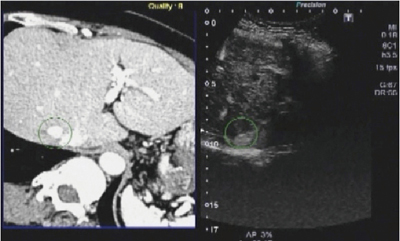

図12は,下大静脈に近接して再発を認めた肝がんの症例である。複数回の治療後,かつ手術後であったことから,超音波での腫瘍の同定が困難であったため,Smart Fusionを施行した。

図12 症例1:51歳,女性,B型,慢性肝炎〜肝硬変,肝S7,11mm,HCC(造影CT)

リファレンスにはCT画像を用いた。軸合わせを行い,対象となる共通部分を選択することで同期が完了する。その後,同定部位確認のために造影を行うと,早期相では強く濃染され,後期相では低造影となり腫瘍部であると確認できた(図13)。

図13 症例1:造影による確認(早期相)

同病巣は,かなり深部で観察は容易ではなかったが,Smart Fusionを用いることで確実に病変部を描出することができ,無事にRFAを施行することができた。